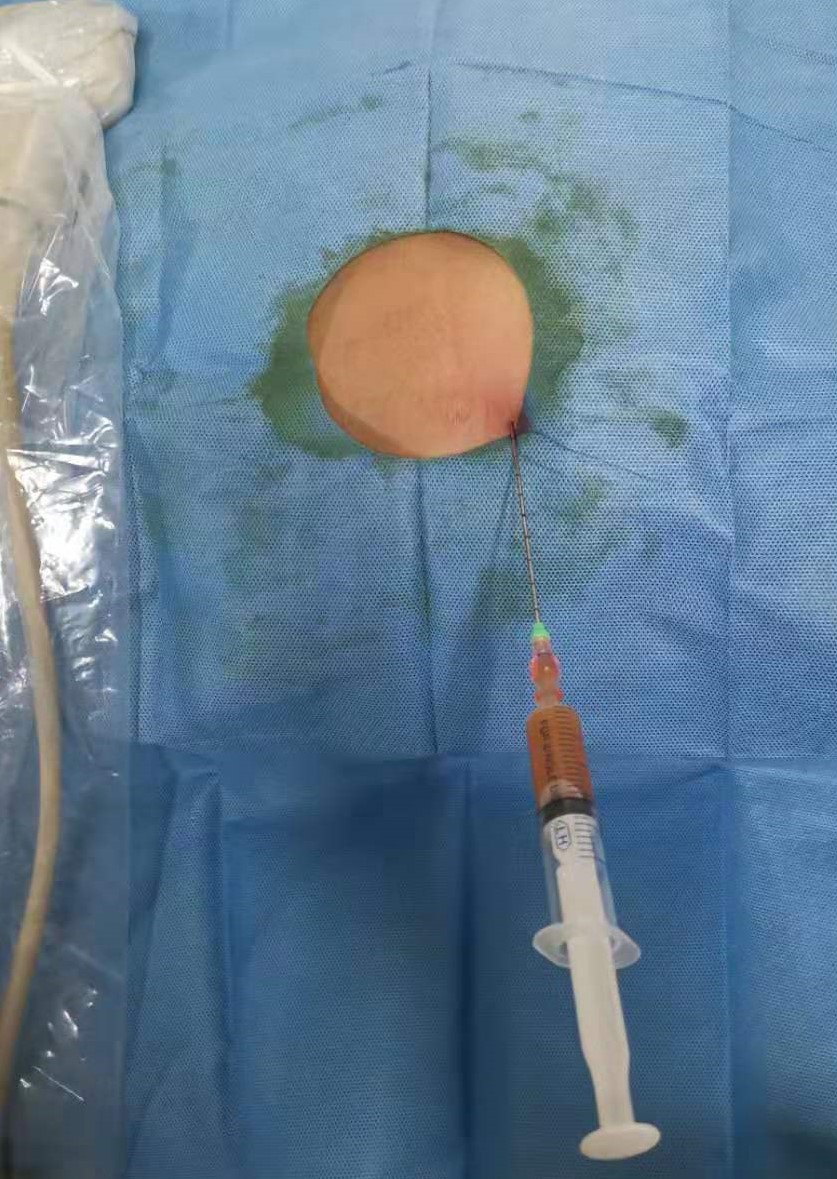

1 资料与方法 1.1 一般资料患者马某某,男,15岁,2019年9月10日以“阑尾切除术后伴腹痛发热6 d”入院。患者8 d前无明显诱因下出现右下腹痛,考虑“急性阑尾炎”,6 d前在当地医院行“阑尾切除术”,术后患者下腹部有持续性疼痛,伴有发热,最高39.3℃,查腹部CT显示:盆腔深部脓肿(图 1),给予抗感染治疗效果不佳,转至蚌埠医学院第一附属医院急诊外科。

| 图 1 下腹部CT显示:盆腔深部脓肿,被肠管,膀胱,骨盆遮挡 |